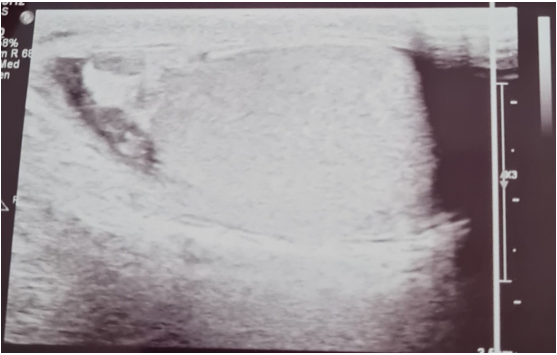

His WBC, CRP, and UFR remained positive after six weeks despite several courses of antibiotics. Then, he started to develop a low-grade fever with loss of appetite and nausea. There was no specific pattern for the occurrence of the fever. A few days later, the scrotal lump started to discharge purulent material through an opening in the skin. An ultrasound scan of the scrotum showed enlargement of the left epididymis with multiple small abscesses along it, indicated by heterogeneously hypoechoic areas along the length of the organ. (Figure 1) A large abscess was noted to have perforated into the subcutaneous tissue forming a small collection in the anterolateral region. The contralateral epididymis appeared normal. Both testes were normal in size, echotexture, and vascular flow (Figure 2).

Figure 1 Ultrasound images showing abscesses in the epididymal head (red arrow) and along the body of the epididymis (black arrows).

Figure 2 Contralateral epididymal head with normal appearance.